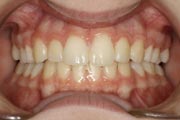

Crowding

After